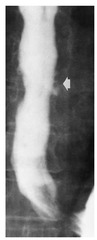

peptic ulcer of lower esophagus, often with stricture

barrett esophagus

Back